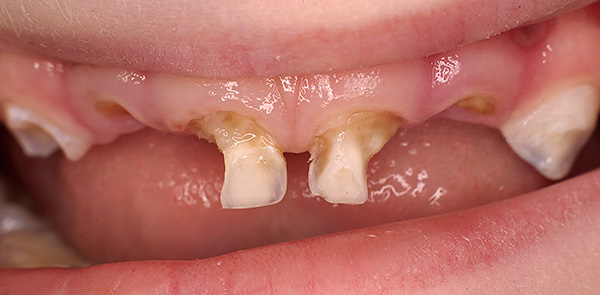

Às vezes, existe um conceito absolutamente errado dos pais de que, como os dentes de leite são temporários, você não precisa cuidar deles. Eles dizem que vão cair de qualquer maneira, e então já será possível fazer uma higiene mais completa. Com essa abordagem, a condição dos dentes do bebê em um bebê pode ser verdadeiramente catastrófica:

É importante entender que problemas na mordida do leite inevitavelmente terão um efeito prejudicial na mordida permanente e, às vezes (mesmo com processos inflamatórios graves), até os rudimentos de futuros dentes permanentes podem ser danificados.